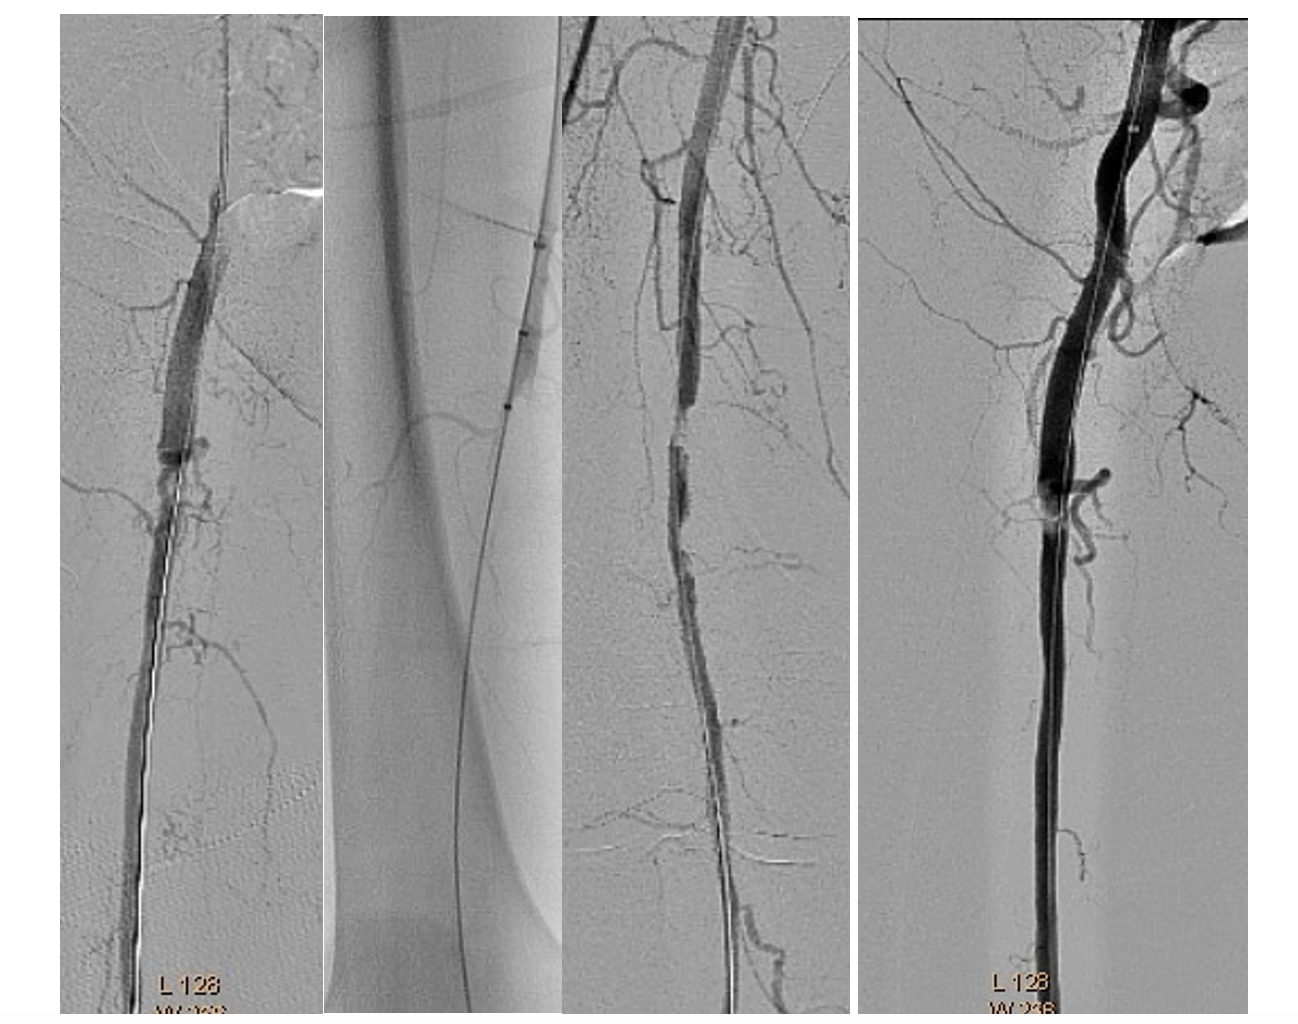

The same introducer was redirected with the tip in the right common femoral artery. PTA of the right SFA, PFA, and popliteal and posterior tibial arteries was performed. Recanalization with a 0.035" Stiff Glidewire (Terumo) and a NaviCross Support Catheter (Terumo). The “riding” thrombus at the SFA/PFA bifurcation then migrated distally and occluded the SFA and PFA (Figure 8). We began EVT from the proximal segment of the SFA, with the same 2.06 mm AngioJet Solent Omni catheter. EVT was performed in the middle segment of the SFA and the popliteal artery (Figure 9). Due to residual thrombosis in the distal segment of the SFA, a balloon dilatation with a 5/120 mm Armada catheter (Abbott) was done (Figure 10).

Thereafter, the right PFA was recanalized with a 0.035" Angulated Glidewire (Terumo) and again EVT was performed with the 2.06 mm AngioJet Solent Omni (Figure 11).

Balloon dilatations in the posterior tibial and tibiofibular trunk were done with 2/120 mm and 3/120 mm Pacific Plus balloons (Medtronic). Because of persistent thrombosis in the proximal segment of the posterior tibial artery, EVT was again performed with the 2.06 mm AngioJet Solent Omni. Finally, distal blood flow was restored in the right SFA, PFA, and popliteal and posterior tibial arteries (Figure 12).